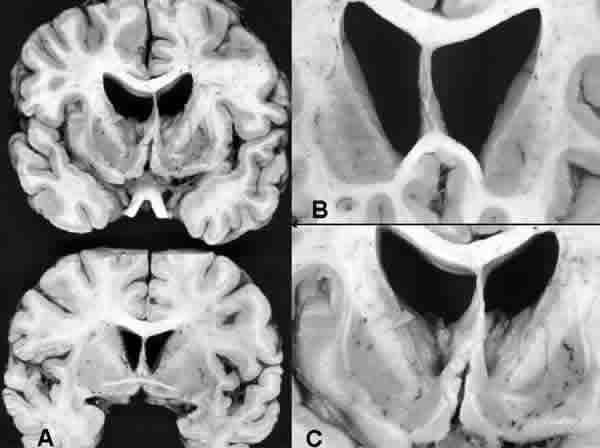

Fig. 1. Alteraciones macroscópicas en la enfermedad de Huntington. A) Cortes sagitales correspondientes a un cerebro con EH (imagen superior) y a un control normal (corte inferior). En la EH se aprecia atrofia de la cabeza del núcleo caudado, que muestra un perfil medial recto en vez del convexo normal, provocando dilatación ventricular. También hay atrofia del putamen. B y C) Detalles de la anterior en cortes realizados a nivel de la cabeza del caudado (A) y del lenticular (B):